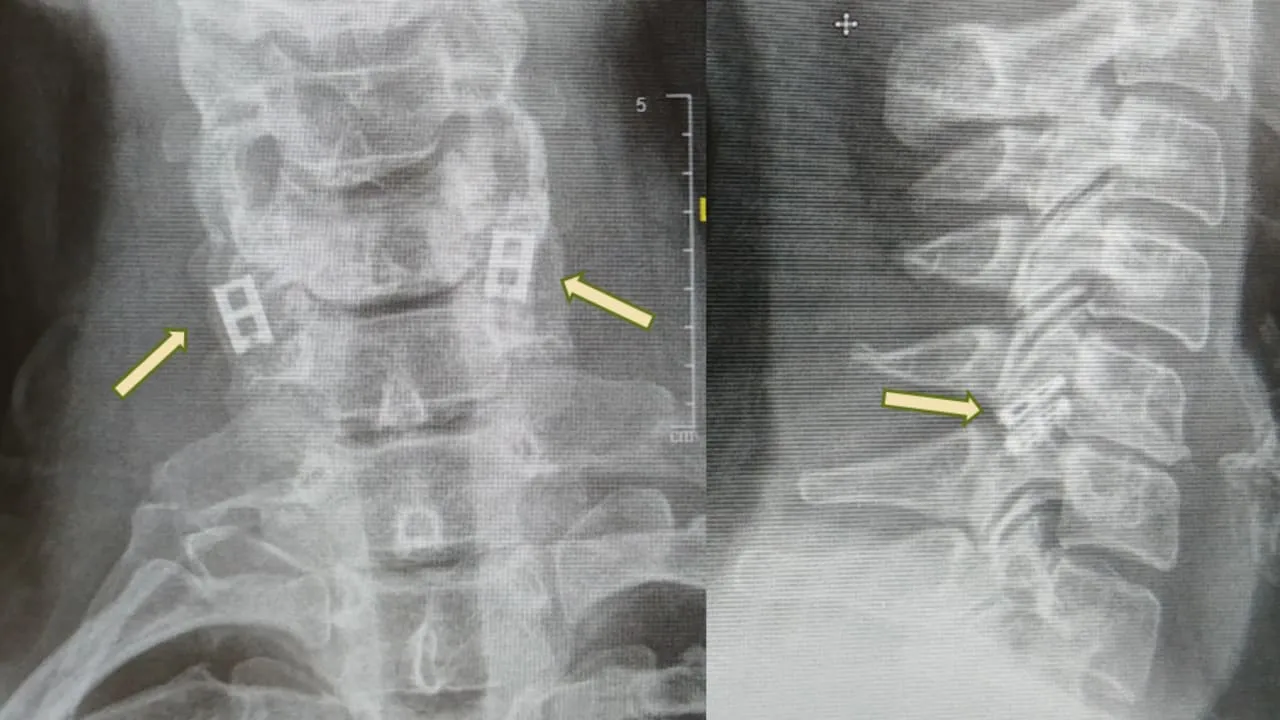

Προς το παρόν, οι τραυματισμοί του νωτιαίου μυελού δεν μπορούν να θεραπευτούν πλήρως, επομένως η θεραπεία επικεντρώνεται στη σταθεροποίηση του ασθενούς, την πρόληψη περαιτέρω προβλημάτων και τη μεγιστοποίηση της λειτουργικότητας. Η επείγουσα φροντίδα περιλαμβάνει συχνά την ακινητοποίηση της σπονδυλικής στήλης, τη μείωση της φλεγμονής και σε ορισμένες περιπτώσεις τη χειρουργική επέμβαση για αποκατάσταση καταγμάτων ή την ανακούφιση από πίεση.

«Ο νωτιαίος μυελός μεταδίδει ηλεκτρικά σήματα από τον εγκέφαλο σε όλα τα μέρη του σώματος. Όταν διακοπεί από τραύμα – όπως τροχαίο ατύχημα, πτώση ή τραύμα μάχης – η αλυσίδα διακόπτεται. Σκεφτείτε ένα ηλεκτρικό καλώδιο που έχει κοπεί: όταν τα δύο άκρα δεν έρχονται πλέον σε επαφή, το σήμα δεν μπορεί να περάσει και ο ασθενής παραμένει παράλυτος κάτω από το σημείο του τραυματισμού», εξήγησε ο καθηγητής Ταλ Ντβίρ, επικεφαλής του Κέντρου Αναγεννητικής Βιοτεχνολογίας Σαγκόλ και του Κέντρου Νανοτεχνολογίας στο Πανεπιστήμιο του Τελ Αβίβ, ο οποίος ηγείται της προσπάθειας. Ο Ντβίρ είναι επίσης ο επικεφαλής επιστήμονας της Matricelf, της ισραηλινής βιοτεχνολογικής εταιρείας που εμπορευματοποιεί την τεχνολογία.